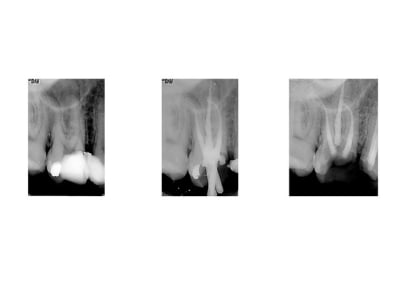

Dans le meilleur des cas, il faudra débarrasser moignon et intrados du ciment résiduel ( quelquefois à la fraise, le plus souvent aux ultra-sons), décontaminer le tout (trempage de la couronne dans NaClO 5%), resceller, recontrôler l'occlusion.